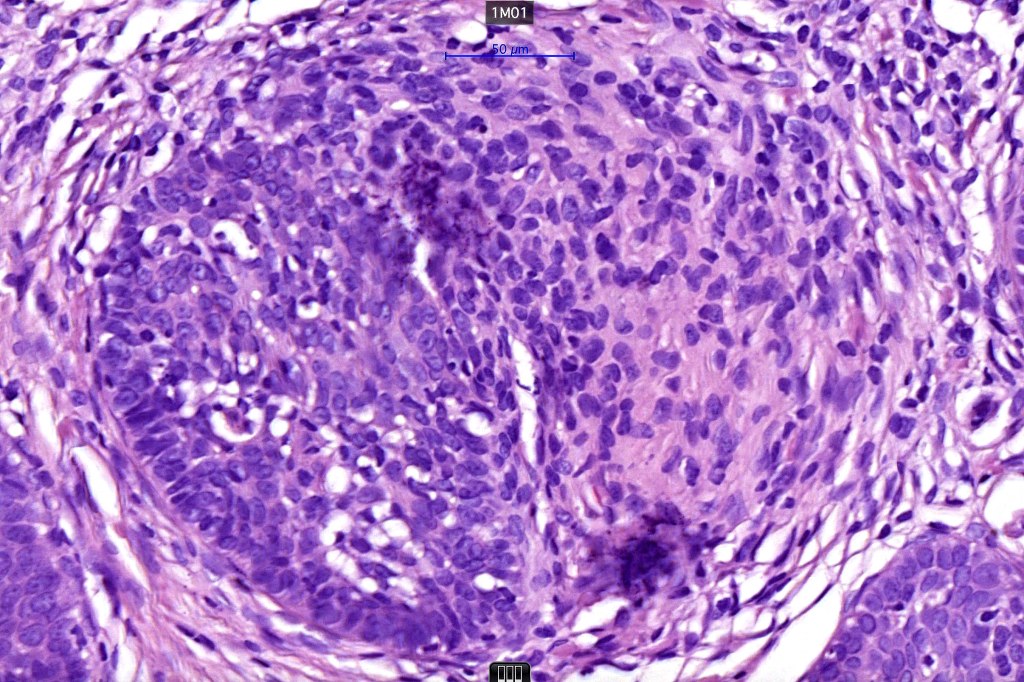

Histological features

•The classical appearance consists of keratocysts & lobules of basaloid cells

•Basaloid lobules show peripheral palisading

•Perifollicular mesenchyme is always conspicuous and sometimes densely aggregated are seen indenting the baslaloid lobules (papillary mesenchymal bodies)

Trichoepithelioma should be distinguished from trichoblastoma since the latter is very rarely syndromic. Trichoepithelioma is largely a dermal tumor whereas trichoblastoma often extends from the dermis into subcutaneous fat or deeper in very large examples. Papillary mesenchymal bodies are much better formed and generally more obvious in trichoepithelioma. Trichoepithelioma must also be distinguished from basal cell carcinoma. Retraction artifact & stromal mucin are features of basal cell carcinoma and not trichoepithelioma. Papillary mesenchymal bodies are not seen in basal cell carcinoma.